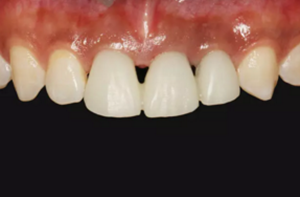

圖2 術(shù)前口內(nèi)像

圖14 術(shù)后4個月口內(nèi)像

圖16 軟組織成形后口內(nèi)像